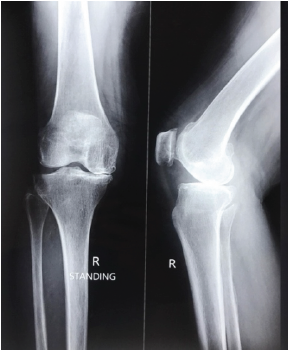

Unusual Case of Failure of Tibial Polyethylene Insert Locking Mechanism in a Design of Cruciate Retaining Total Knee Arthroplasty – A Case Report

Chandan Mehta , Mohan Madhav Desai , Kushagra Jain , Urvil Shah